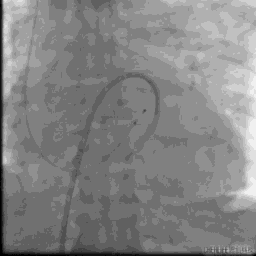

球囊跨二尖瓣

24MM二尖瓣球囊扩张